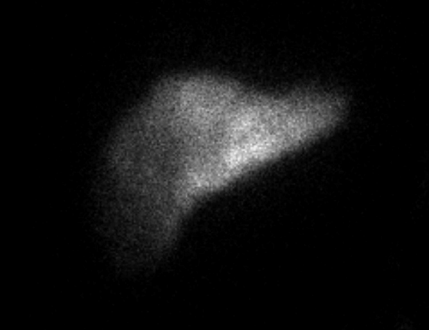

The patient notably had undergone two right thoracenteses demonstrating transudative fluid characteristics (Table 1). The patient had multiple interrogations of his hepatic artery infusion pump, including a nuclear medicine hepatic pump with SPECT/CT (Image 2) and an IR venogram (Image 3), demonstrating adequate position and functioning of the hepatic artery infusion pump with appropriate perfusion of the liver and no evidence of extrahepatic radiotracer. The patient’s labs preoperatively were all within normal limits, including normal biliary labs with AST/ALT 23/15, AP 55, and total bilirubin .3.

Image 2. IR Procedure: NUC MED HEPATIC PUMP with SPECT/CT

IMPRESSION: Appropriate perfusion of the liver after injection of radiotracer into the hepatic arterial infusion pump. No evidence of extrahepatic radiotracer collection identified.